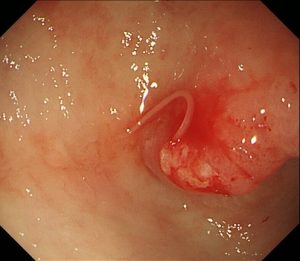

1匹目です。胃の前庭部(奥の方)に食いついています。

鉗子で除去していきます。